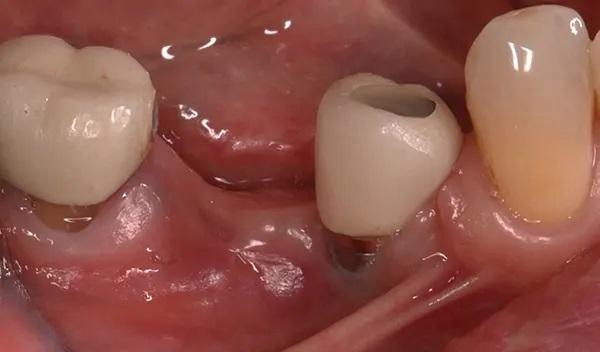

Пациент приходил для осмотра через 1, 2, 4, 6 (снятие швов), 8, 12, 16 и 24 недели (фото 10). Пациент четко соблюдал рекомендации, поэтому отлично контролировал образование зубного налета. Положенные раз в полгода процедуры по профилактике были проведены в срок 14 недель после проведенного вмешательства. Клиническое обследование через 24 недели выявило увеличение объема как горизонтального, так и вертикального альвеолярного отростка (фото 11) по сравнению с исходным уровнем (фото 3 –фото 5).

Фото 11. Окклюзионный вид десны через 24 недели после НКР. Бросается в глаза новая морфология щек и наличие ороговевшей ткани.